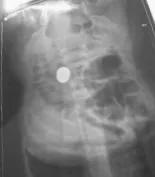

宝妈带宝宝去医院拍了片子,大夫说硬币已经进到胃里了,多吃点有助于排便的食物,让宝宝自己排出来。 大夫还把我朋友给训了一顿,说她带孩子太粗心了[快哭了][快哭了]

硬币已到了胃里